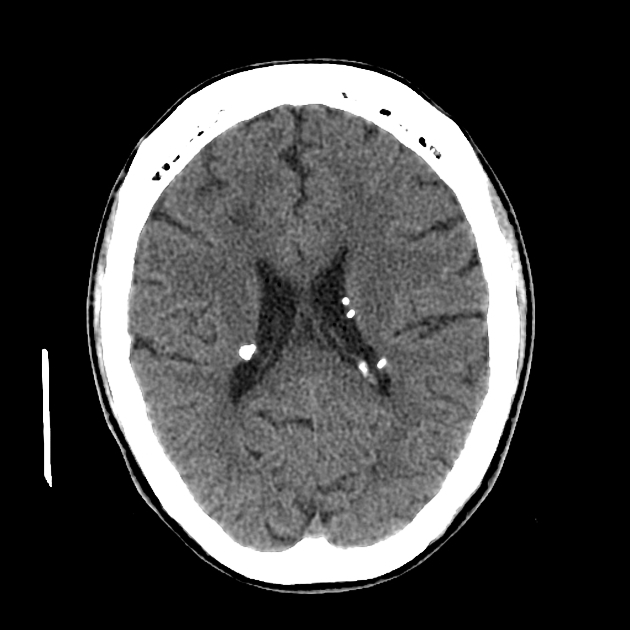

Компьютерная томография при подозрении на туберозный склероз проводится в режимах нативного сканирования головного мозга и органов грудной и брюшной полости. Цель обследования — выявление кальцифицированных кортикальных и субэпендимарных узелков, а также других аномалий, типичных для туберозного комплекса, включая поражения лёгких, почек и костей.

КТ выявляет следующие признаки туберозного склероза:

Множественные субэпендимарные узелки вдоль стенок боковых желудочков, с плотностью от +40 до +120 HU, часто с участками кальциноза.

Кальцифицированные кортикальные туберы в области лобных и теменных долей, реже — затылочной, чаще асимметрично.

Субэпендимарные гигантоклеточные астроцитомы в переднем роге бокового желудочка с мягкотканной плотностью и возможным эффектом объёма.

- Точная визуализация кальцифицированных субэпендимарных узлов и кортикальных туберов, особенно у детей.

- Контрастное усиление позволяет отличать астроцитомы от неусиливающихся субэпендимарных узлов.